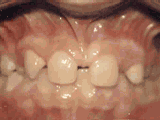

Protruding teeth, anterior teeth protrusion, and certain teeth rotation. After a professional assessment, extraction of one tooth on each side of the upper and lower jaws, followed by orthodontic treatment, resulted in the transformation shown here.